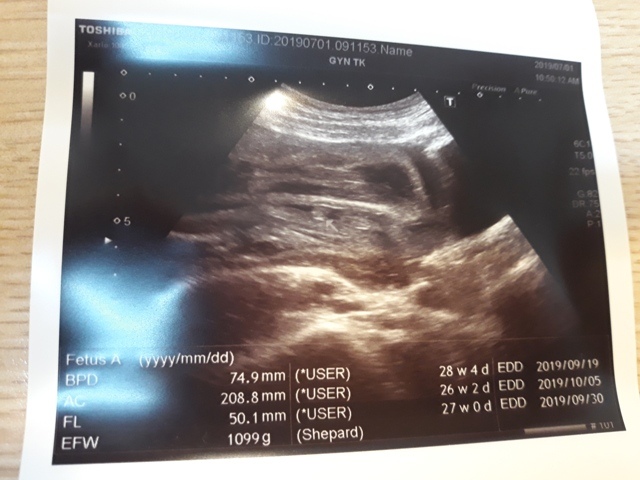

妊娠糖尿病數值為124,超過140就是超標,小純的妊娠糖尿病檢驗結果為正常的數值。接著,去照超音波,自從05月22日和06月03日的產檢,發現小飛的FL(腿長)比實際天數少一個星期後,讓小純感到很鬱悶,他最近很努力的吃鈣片,希望能讓小飛的腿長趕上進 度,今天一量,27週又0天,雖然還是落後實際的天數(27週又3天),但已漸漸趕上了。

27週又3天↓

近六次產檢資料統計

| 日期/項目 | BPD | AC | FL | EFW | 心跳 |

| 2019年03月04日 | 無資料 | 無資料 | 無資料 | 無資料 | 無資料 |

| 2019年04月01日 | 28.9mm | 77.9mm | 14.2mm | 107g | 153 |

| 2019年04月29日 | 41.7mm(44%) | 125.7mm(61%) | 28.9mm(103%) | 241g(125%) | 150 |

| 2019年05月22日 | 53.4mm(28%) | 160.6mm(28%) | 34.6mm(20%) | 408g(69%) | 150 |

| 2019年06月03日 | 58.3mm(9%) | 179.6mm(12%) | 38.2mm(10%) | 584g(43%) | 157 |

| 2019年07月01日 | 74.9mm(28%) | 208.8mm(16%) | 50.1mm(31%) | 1099g(88%) | 141 |

| BPD:胎兒頭骨橫徑 AC:胎兒腹圍的長度 FL:胎兒大腿骨的長度 EFW:胎兒的體重 括弧內百分比為較上次產檢的成長比例 | |||||